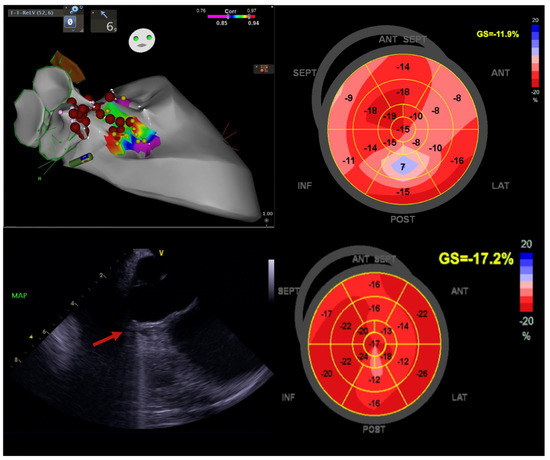

Figure 6. Image emphasising the significance of PVC ablation in a 60-year-old male diagnosed with HFmrEF. Initially, his left ventricular ejection fraction (LVEF) percentage stood at 42%, and his global longitudinal strain (GLS) measured −11.9%. The baseline PVC burden was noted at 22%, with PVCs localised to the right para-Hisian region. Intracardiac echocardiography unveiled a basal septal scar (indicated by a red arrow) positioned just below the right coronary cusp (RCC). At the one-year follow-up, the PVC burden plummeted to 1.2%, accompanied by an improvement in LVEF to 66% and GLS to 17.2%. This case highlights the pivotal role of PVC ablation in ameliorating left ventricular function and enhancing quality of life. Image courtesy of the Canberra Heart Rhythm Centre.